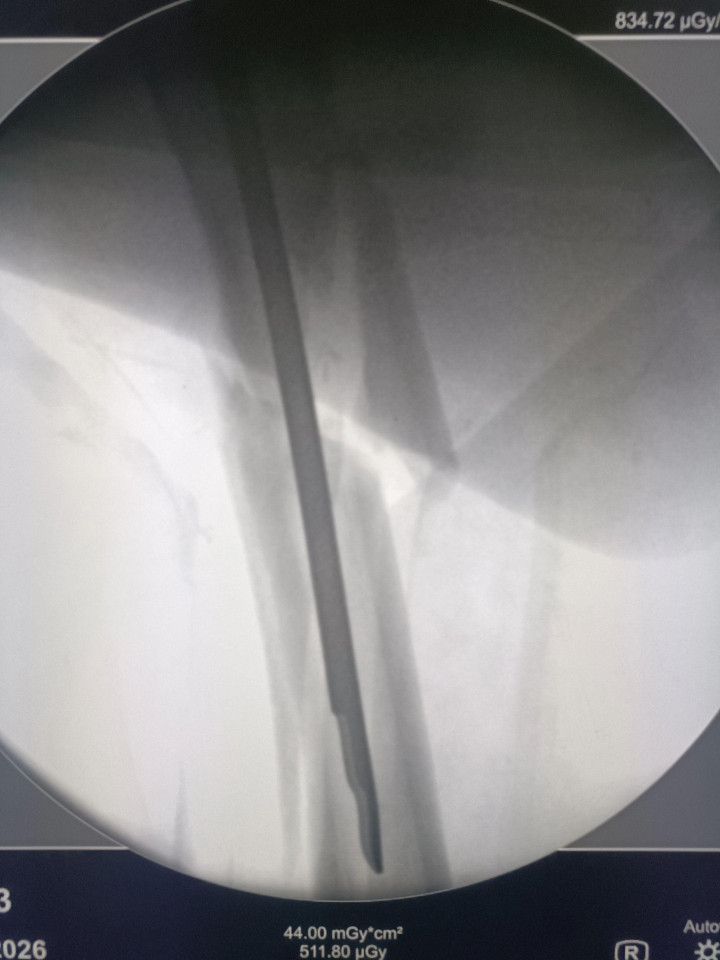

中股网 外伤导致的股骨上段骨折闭合复位股骨重建钉固定,期待早期愈合